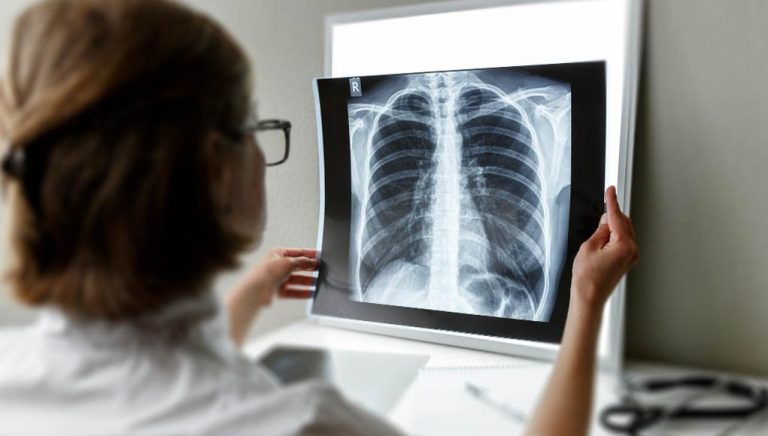

أفادت وزارة الصحة والحماية الاجتماعية بأن معطيات سنة 2025 بالمغرب أظهرت أن 53 في المائة من حالات السل الجديدة المسجلة تتعلق بالأشكال خارج الرئة، وذلك في سياق تخليد اليوم العالمي لمكافحة السل لسنة 2026، الذي ينظم هذه السنة تحت شعار يركز على تجاوز السل للرئتين وتعزيز الوعي بالأشكال غير الرئوية.

وأوضحت الوزارة في بلاغ رسمي أن هذه المؤشرات تستدعي تكثيف جهود التوعية الصحية، وتعزيز اليقظة السريرية لدى مهنيي الصحة، بما يساهم في تحسين التشخيص المبكر وضمان التكفل الملائم بالحالات، مؤكدة أنها تواصل، على غرار باقي دول العالم، تعزيز تدخلاتها للكشف والتكفل بمختلف أشكال هذا المرض.

وأشار البلاغ إلى أن تخليد هذه المناسبة يروم دعم التحسيس بداء السل، وتشجيع المواطنين على اللجوء المبكر إلى الخدمات الصحية، إلى جانب مواكبة مهنيي الصحة في التعرف على الأشكال خارج الرئة والتعامل معها، مبرزا أن نسخة 2026 تولي اهتماما خاصا بهذه الأشكال التي لا تزال غير معروفة على نطاق واسع، وغالبا ما يصعب تشخيصها رغم حضورها ضمن الوضع الوبائي الوطني.